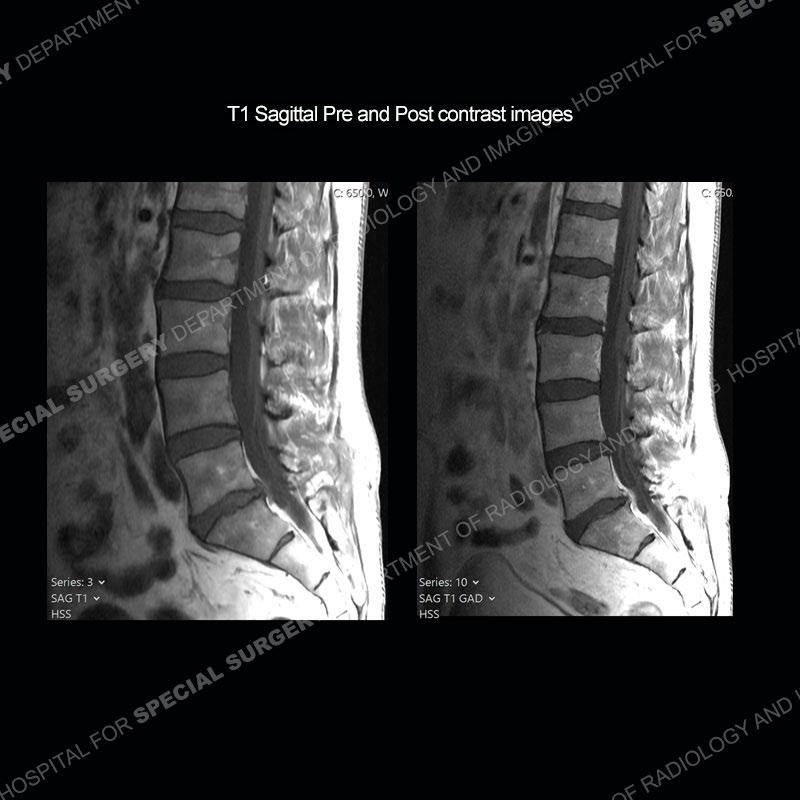

Post operative changes are seen on the left side at L5-S1 where there is near complete removal of the left sided L5 lamina, partial resection of the left L5-S1 facet joint, and resection of the left sided ligamentum flavum. In the anterolateral epidural space about the subarticular recess is a mass that demonstrates similar T1 and T2 signal characteristics to the adjacent degenerated disc. There is enhancement about the periphery of the mass, but the majority of this somewhat geographic or polyploid mass demonstrates no enhancement. The mass exerts prominent mass effect on the left S1 axillary sleeve/proximal nerve root. The left S1 nerve root shows enlargement and increased enhancement as compared to the contralateral right side.

Not as much of a diagnostic dilemma as some other cases but more so just a very nice example of what can be a difficult assessment at times. The evaluation of granulation tissue/scar/epidural fibrosis vs. disc herniation particularly in the earlier post operative period can be very difficult. Clues that can assist in identifying a disc herniation are a more geographic or polypoid nature to the mass, signal characteristics similar to the adjacent degenerated disc, mass effect upon the thecal sac/adjacent neural structures, and a typical enhancement pattern. As the disc material is avascular, as long as imaging is performed in a relatively rapid fashion after contrast administration (within 20-30 minutes), the granulation tissue around the disc will enhance but the disc material itself will not. If there is a marked delay between contrast administration and imaging, there may be diffusion of contrast into the disc making the assessment very difficult. The marked utility of contrast to help delineate disc vs. scar has led to our institution employing contrast fairly uniformly within the first two years following surgery.

The scar tissue in the setting of prior disc removal will be present in the anterior and anteriorlateral aspect of the epidural space. The signal characteristics can be somewhat variable from slightly more T2 hyperintense earlier on to T2 hypointense as the scar matures. However, the signal does not tend to follow the adjacent degenerated disc. The scar can produce mass effect, but it does not have to do so. In addition, at times the scar may be associated with a retraction of the adjacent thecal sac. Given the vascular nature of the scar there is typically somewhat avid, uniform enhancement which occurs fairly rapidly after contrast administration and begins to diminish within 20 minutes or so. Trying to discern the difference between scar and disc is of paramount importance given the rather poor outcomes associated with resection of scar as compared to disc material.